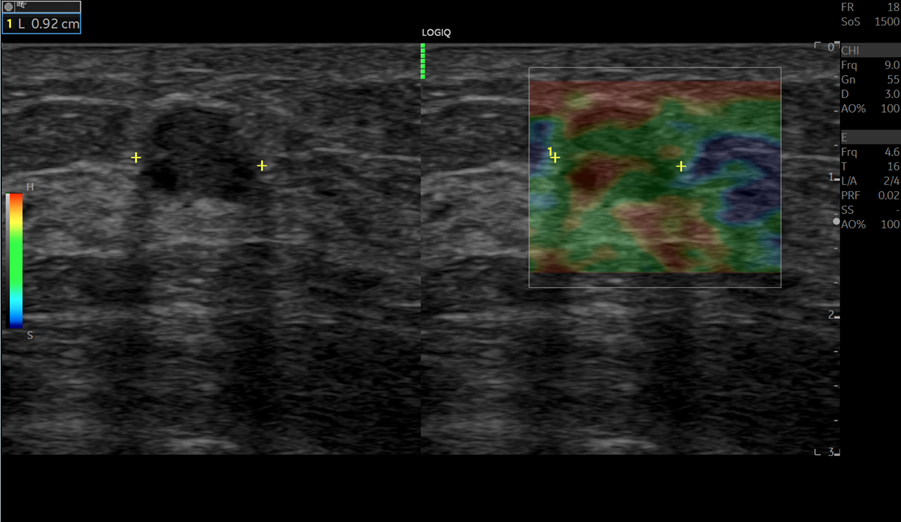

Kết quả Strain Elastography

Bản đồ màu (Siêu âm đàn hồi Strain Elastography)

Đồ thị hiển thị độ đàn hồi theo thời gian (Siêu âm đàn hồi Strain Elastography)

Bản đồ màu đàn hồi cho thấy vùng khối u chủ yếu có màu xanh lá, gợi ý mô mềm so với mô xung quanh. Các chỉ số bán định lượng ghi nhận:

- Điểm đàn hồi (ES): 2.

- Strain Ratio (SR): 2,4.

- E/B (DR) < 1.

Những thông số này cho thấy độ cứng của tổn thương chỉ cao hơn nhẹ so với mô lành, hướng nhiều đến tính chất lành tính.